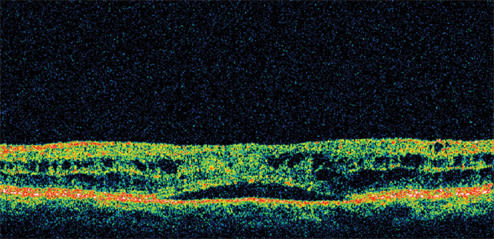

Figure 3. By 12 weeks, the patient's visual acuity had improved to 20/20 with a reduction in retinal thickness of 262 μm from her pretreatment status.

Presenting visual acuity was 20/40. Her IOP was 23 mm Hg and retinal thickness was 478 μm on OCT (Figure 1). She was treated with nepafenac qid for 6 weeks and tapered over the ensuing 6 weeks. Her vision improved to 20/25 by 1 month with significant reduction in her retinal thickness (Figure 2). By 12 weeks, her visual acuity had improved to 20/20 with a retinal thickness of 216 μm and a normal foveal contour. This represents a reduction in retinal thickness of 262 μm from her pretreatment status (Figure 3). However, she continued to report a mild reduction in contrast sensitivity.